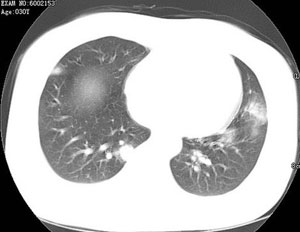

女性,30岁。

病史为胸痛20多天,无畏寒发热,无消瘦,无咳嗽咳痰。总之症状很逍遥。

临床以胸痛待查收住入院。

双肺野可见散在大小不等结节及肿块影,内密度不均匀,边缘部分清,部分欠清,纵隔未见明显肿大淋巴结.右侧胸腔少理积液.结合临床,考虑韦格肉芽肿可能吧,巨淋巴增生,结节病,特殊感染都要考虑.转移瘤临床不象.

本病例特点如下:

1.青年女性,以胸痛20多天就诊,无呼吸道及感染临床症状体征,无原发肿瘤病史;

2.肺ct表现为两肺多发大小不等结节影,大结节位于肺尖部,小结节多位于肺外带胸膜下,大结节内可见支气管充气征,周围可见月晕征(指在结节状或肉芽肿样病灶周围呈环形磨玻璃影),右肺门及腔静脉后可见小淋巴结,右侧胸腔内少量液体。

两肺散在分布大小不等的肿块及结节影,边缘毛糙,有分叶、毛刺,病灶密度不均匀,可见支气管充气相与空泡征。病变大多位于胸膜下,可见胸膜凹陷及胸腔积液。气管腔静脉间可见小结节影。